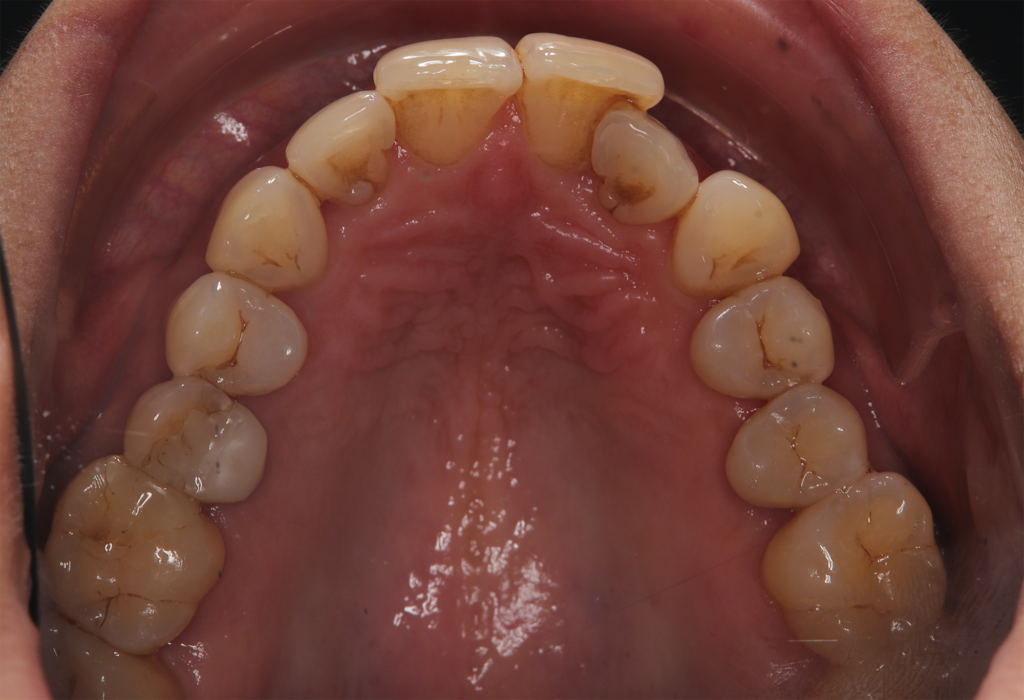

The patient, having completed a periodontal treatment phase, presented with significant aesthetic and functional concerns due to moderate crowding in both arches and a pronounced anterior crossbite. Clinical examination confirmed the need for comprehensive realignment, particularly in the anterior region. Although the patient had a history of periodontal issues, radiographic evaluation showed no signs of active disease. Based on these findings, the treatment plan was designed to carefully modulate orthodontic forces to protect the occlusion and surrounding tissues while addressing the misalignment.

To correct the misalignment and anterior crossbite without compromising tissue stability, a slower orthodontic treatment plan was devised using the Spark Advanced clear aligner system. The initial phase involved 36 aligners designed to gently expand and realign the dental arches, limiting the rate of tooth movement. Strategic interproximal reduction (IPR) was performed in the anterosuperior region (between teeth #21 and #11) to create the necessary space for proper alignment while avoiding excessive loading on the tissues.

To refine the results and enhance aesthetics, a second phase incorporating an additional 17 aligners was introduced. During this refinement stage, careful IPR in the lower arch helped harmonize the midline and achieve a balanced occlusion. Once satisfactory alignment was reached, provisional composite restorations were placed on the upper lateral incisors to aesthetically close any interproximal gaps.

At the conclusion of the treatment, the patient achieved excellent dental alignment and a stable occlusal relationship, particularly in the anterior region. Radiographs and clinical assessments confirmed that there was no further bone loss and that previous improvements were maintained. The aesthetic enhancement from the composite restorations further contributed to the overall success of the treatment.